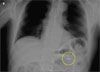

An abdominal radiograph showed what appeared to be a small light bulb in the left upper quadrant (A). This study was compared with a film of the same patient obtained 3 years earlier that also showed a foreign body (B). There was no mention of this object in the accompanying radiology report. A CT scan of the abdomen revealed a metallic foreign body (about 2.3 x 1.2 cm) in the region of the descending portion of the duodenum.

An upper endoscopy was performed. The foreign body was located in the bulb of the duodenum and was retrieved intact with a basket and overtube (C). The specimen was identified as a broken light bulb (D), with a 1 x 1-cm glass portion and 1.2 x 0.7-cm metallic portion. At follow-up, the patient’s GI symptoms had diminished.